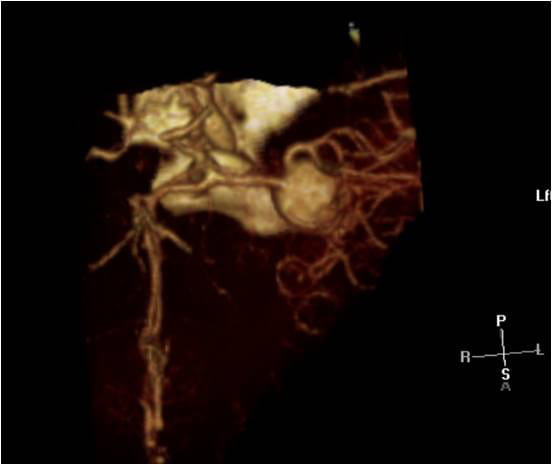

This video documents the surgical clipping of a giant middle cerebral artery aneurysm. The patient is a 56-year-old woman with a Grade I subarachnoid hemorrhage.

Supplemental photos also accompany the video below.